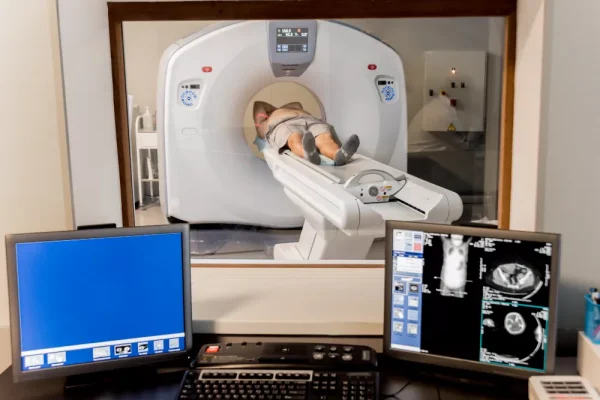

- Tetkikler

- Hizmetler